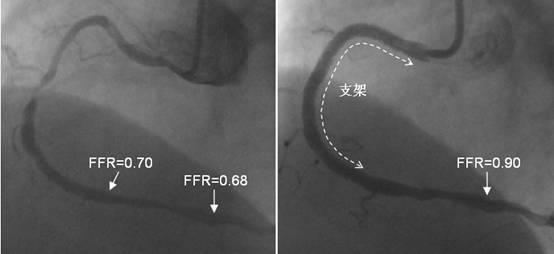

这种检查能够测出狭窄血管到底有没有缺血,而不仅仅是介入医生根据自己的经验进行判断。血管内超声可以测量狭窄更准确的比例;FFR>80%则说明没有心肌缺血,不用放支架;FFR<75%则说明有心肌缺血,需要放支架。

所以放不放支架,需要结合临床症状及冠脉造影,如果仍不能肯定病变是否有缺血,那么建议血管内超声及FFR检查,给出一个更为客观的证据。